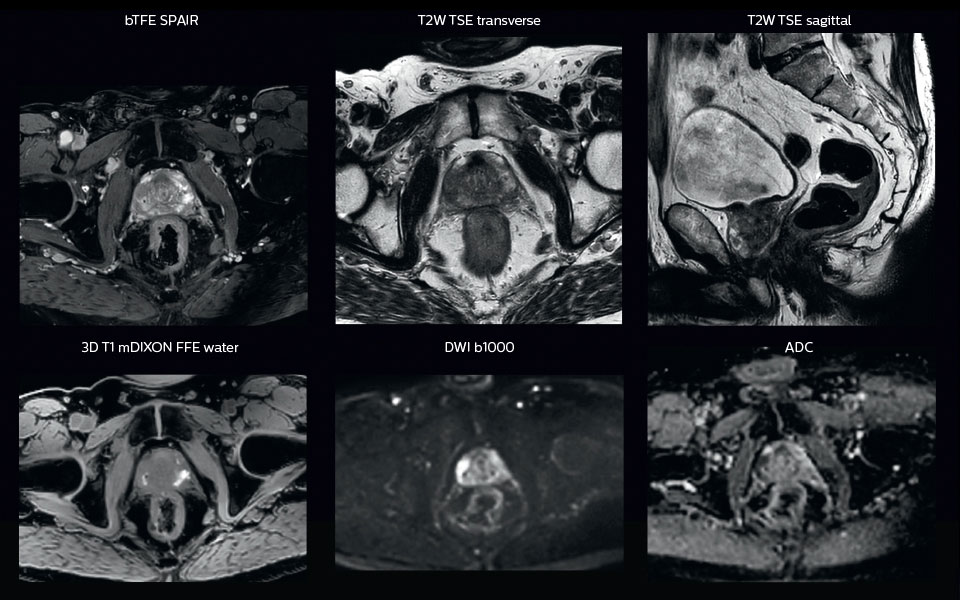

A 63-year-old patient with prostate cancer, cT3bNxM, Gleason 7, underwent MRI on Ingenia 3.0T MR-RT before radiation therapy.

Intraprostatic lesions are visible on the bTFE MR image, but not on the CT image. MRI shows excellent soft-tissue contrast for the visualization of critical structures like the rectum and penile bulb.

Fiducial markers (green arrows) are used in registration of MR images to CT, to transfer the MR-based delineations onto the CT image dataset.